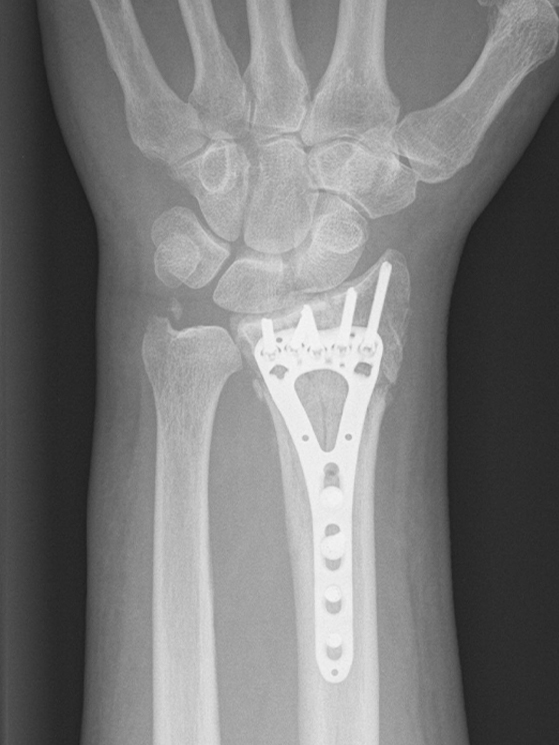

Possiamo dire che se l’hanno operato è sicuramente una frattura scomposta che necessitava di un intervento chirurgico. C’è da dire che negli atleti di alto livello spesso e volentieri succede che se c’è il dubbio di operare o meno si cerca di effettuare l’intervento chirurgico e avere quindi una certezza di un recupero magari migliore e in tempi più brevi. Mettendo una placca, il recupero e la calcificazione ossea avviene meglio e prima.

Ridurre e stabilizzare la frattura. Di solito viene posizionata una placca che si salda con delle viti che devono garantire la stabilità della frattura. Questa stabilità velocizza anche il callo osseo. Il velocizzare il callo osseo, ci permette di ottimizzare la ripresa. Dopo l’intervento vieni immobilizzato mettendo un gesso o in questo caso viene sostituito oggi da dei tutori termoplastici. Questo permette di far muovere le dita fin da subito all’atleta e non perdere quella parte di funzionalità che è importante tenere attiva.

Sono fratture che si possono risolvere nel giro di 5 o 6 settimane. A distanza di 15 giorni si fa una radiografia di controllo e si valuta che tutto vada bene. Si valuta se il tutore può essere già tolto per fare della fisioterapia antifiammatoria e passiva. Essendo un ciclista gli si può fare un tutore particolare per pedalare sui rulli già dopo una quindicina di giorni.

C’è un recupero effettivo. Più avanti ci sarà anche la possibilità di rimuovere la placca per evitare che in futuro crei fastidio al polso. Questo avviene di solito dopo un anno.